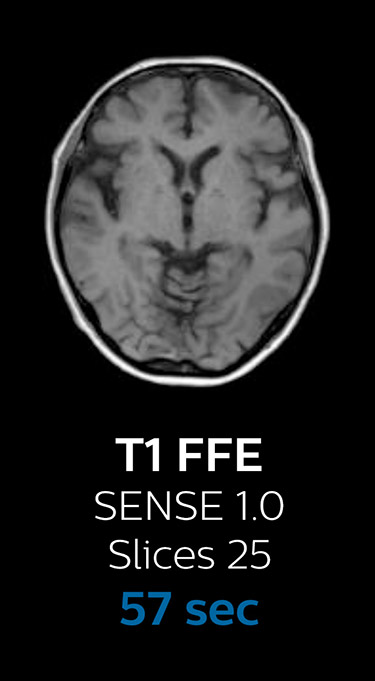

“We now only need about 10 minutes of scan time for a brain exam – and we still get the same amount of images and equal quality. We even managed to make a very useful improvement: we replaced the 43-second T21 FFE by a 43-second SWIp, which is more powerful for us in making confident diagnoses in certain patients.” “SWIp was not previously included in our standard protocol, because of its slightly longer scan time. SWIp provides high resolution 3D susceptibility weighted imaging in the brain, which helps to visualize small deoxygenated blood or calcium deposits. Now, with Compressed SENSE, we can perform 3D SWIp in only 43 seconds, so we have included SWIp instead of the 2D T21 FFE that we used previously. Without adding scan time, we now get SWIp images in every routine brain scan and it helps us increase our diagnostic confidence in certain cases.”

Scanning time reduction in brain MRI with Compressed SENSE

Fast MRI of brain

With Compressed SENSE, the scan time for the routine brain examination at KNC was reduced from 15:48 to 10:19 minutes, which corresponds to 35% reduction.

Ingenia 3.0T CX

Scan time 15:48 min.

Brain with Compressed SENSE

Ingenia 3.0T CX

Scan time 10:19 min.